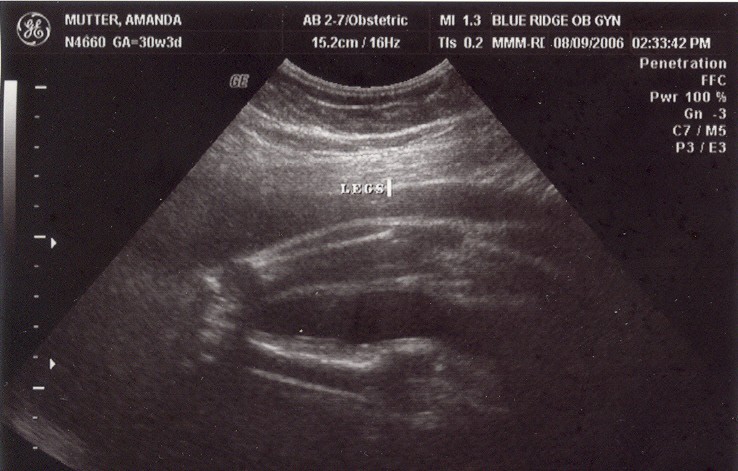

August 8, 2006: Another Ultrasound

Little did my parents know I'd be making my entrance in less than a month. The OB didn't suspect either :-)